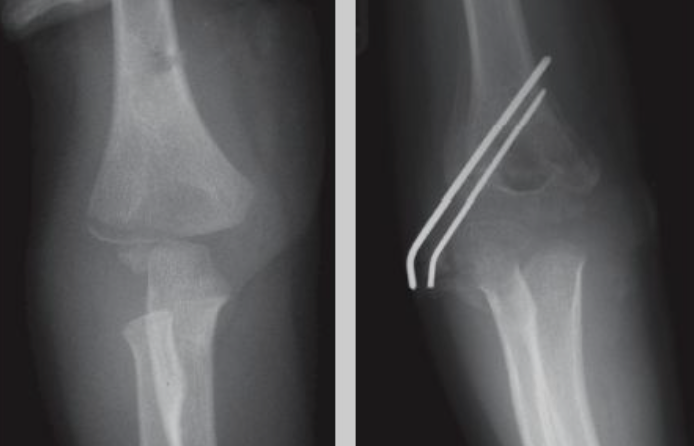

1.비수술적 치료: 대다수의 소아 골절은 뼈의 재생 능력이 뛰어나 석고 고정(기브스) 등 비수술적 치료로도 좋은 결과를 얻을 수 있습니다.

2.수술적 치료: 골절의 전위가 심하거나 관절면, 성장판을 침범한 경우, 또는 비수술적 치료로 정복이 어려운 경우에는 금속 핀, 고정술 등 수술적 치료가 필요할 수 있습니다.

상완골 외과 골절 : 팔꿈치 바깥쪽(외측과) 골절, 팔을 펴고 넘어질 때 발생, 성장판 손상 위험